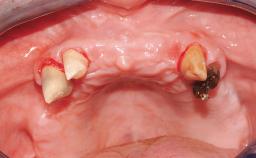

| Jaw | Maxilla and Mandible |

| # of Teeth | 9 |